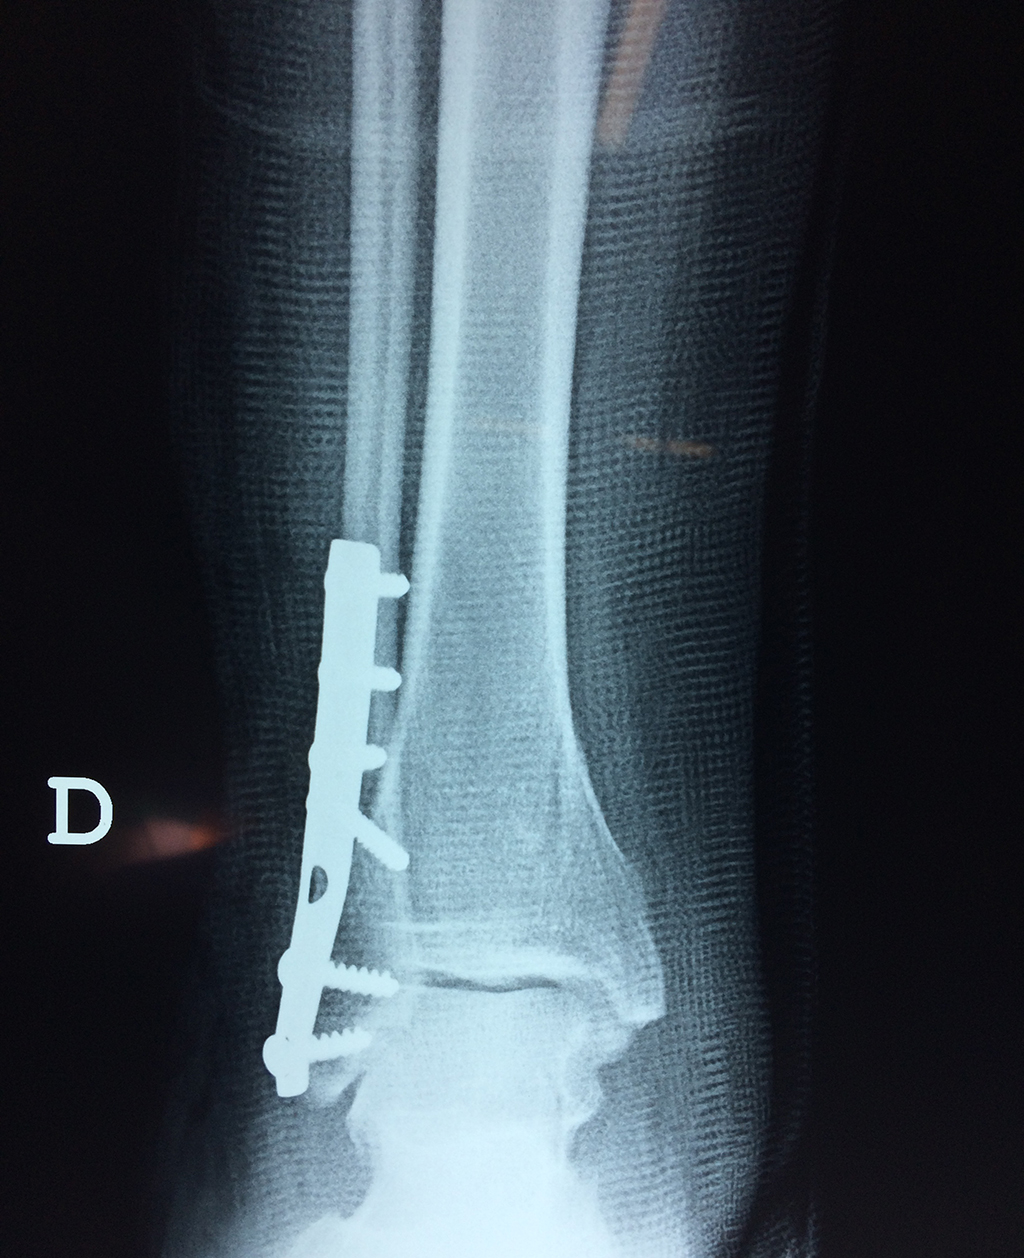

Cuando se necesita cirugía, es probable que esta implique el uso de clavijas de metal, tornillos o placas para sostener los huesos en su lugar mientras la fractura se consolida. Los elementos de soporte pueden ser temporales o permanentes.

Cirugía de Tobi...

Detail Download